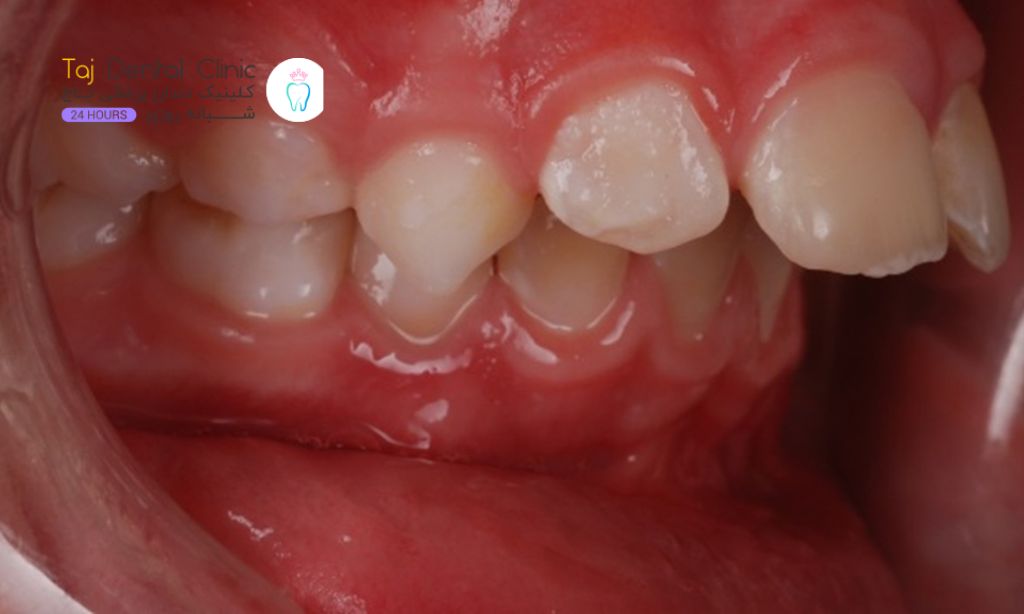

دندانهای خرگوشی به دندانهایی گفته میشود که مجموعه بالایی و پایینی دندانها همتراز نیستند. دندانهای بالا معمولاً بیرون زده و روبه جلو هستند. در مواردی اندک، دندانها ممکن است چند میلیمتر از لب پایین جلو باشند. در موارد بسیاری هم دندانها روی لب پایین کشیده میشوند.

بهتر است بدانید که در بیشتر موارد، دندانهای خرگوشی وضعیتی تهدیدکننده یا خطرناک نیستند. اما این نوع چینش دندانها، وضعیت لبخند شما را تحتتأثیر قرار میدهد. کامپوزیت یکی از راهحلهای پرطرفدار برای زیبایی و اصلاح دندانهای خرگوشی است. کامپوزیت، روی دندان قرار میگیرد و عیوب دندانهای نامرتب را پوشش میدهد. اصلاح دندانهای خرگوشی کمک میکند تا دندانهای صافتر و لبخندی جذابتر داشته باشید.